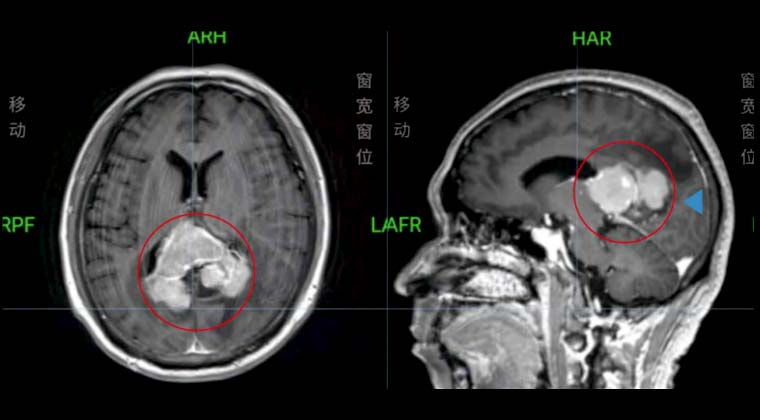

Пациент - мужчина, 49 лет

Диффузная крупноклеточная B-клеточная лимфома

002021 до начала лучевой терапии выполнено обычное и контрастное МРТ головы:

Образование в мозолистом теле, распространяющееся на теменную долю, соответствует лимфоме.

102021 проведена радиотерапия очага в головном мозге с использованием 6MV-X лучей, с одновременным интегрированным бустом: PTV1: 40 Гр / 2 Гр / 20 сеансов; PTV2: 36 Гр / 1,8 Гр / 20 сеансов; 5 сеансов в неделю

Повторное МРТ 002021 показало изменения после лечения лимфомы, очаги в черепе уменьшились по сравнению с предыдущими исследованиями.

До лечения:

После лечения: